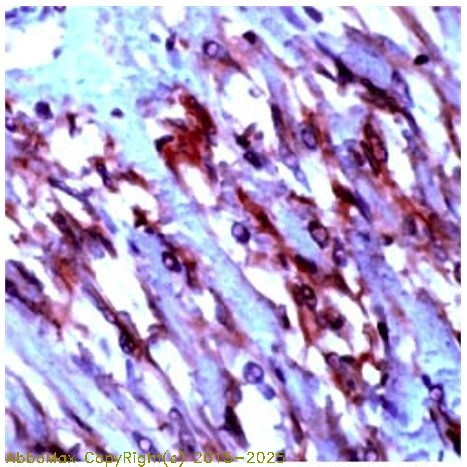

IHC

2-10 µg/ml